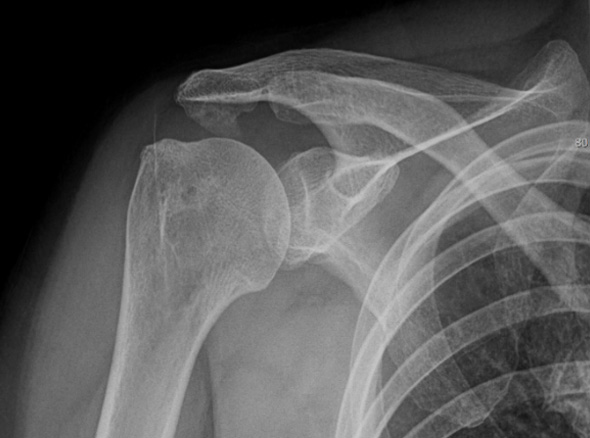

어깨충돌증후군이 발생하게 되면 회전근개에 염증이 발생하게 되고

급성 부종을 일으키게 됩니다.

30대를 시작으로 50대까지 증상이 지속적으로 악화되고 통증도 점차 커집니다.

증상이 심한 경우 일상 생활에 어려움이 발생되어 수술적인 치료를 고려할 수 있습니다.

보존적 치료에 호전되지 않는 경우

회전근개 파열로 진행되고 있는 경우

극심한 통증을 동반하고 있는 경우